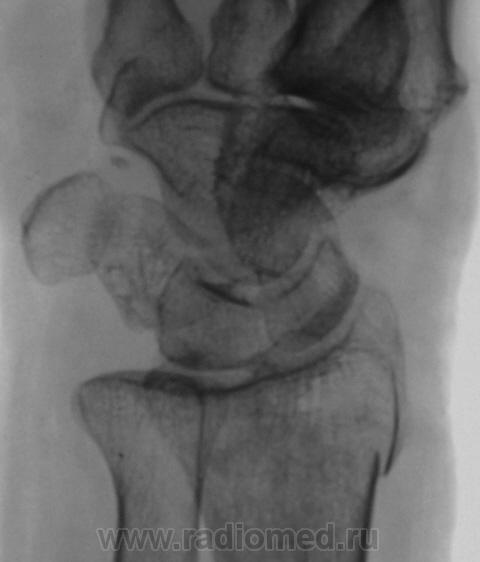

Травма.   Пациент направлен на рентгенографию лучезапястного сустава.